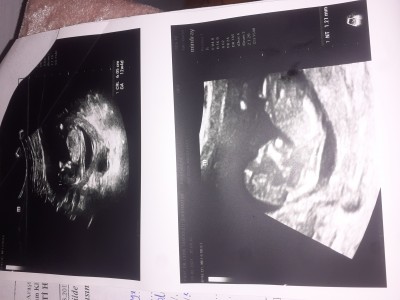

Gecen hafta ikili test yaptik soucumuz budur doktor bana once bisey yok sonra tekrar gel dedyince merak ettim anlayan bakabilir mi

Gebelik haftası 13+ haftalik